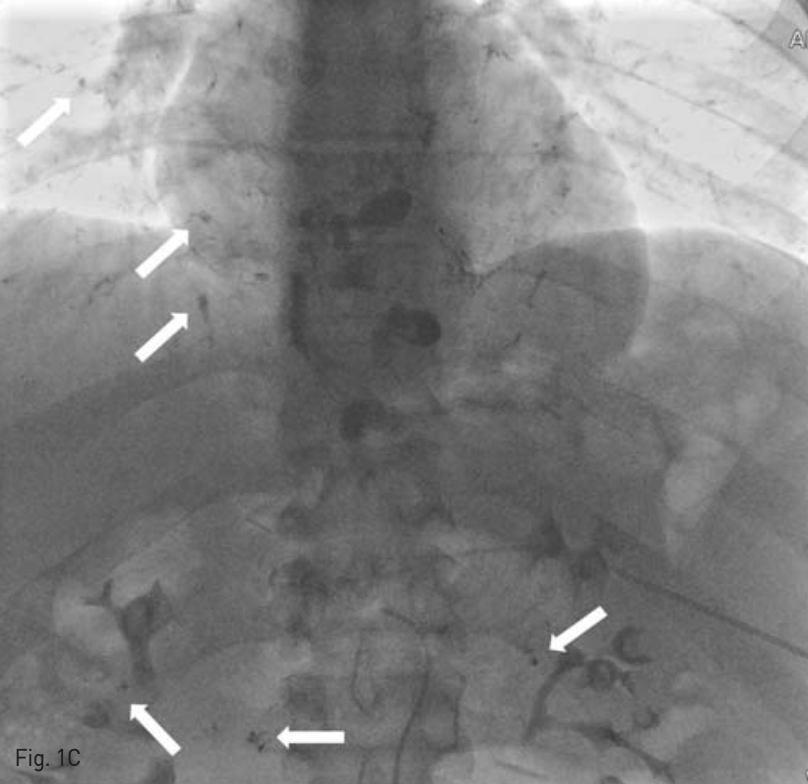

Embolizalion을 시행한 후 추적 정맥조영술에서 esophageal varix를 통한 flow는 대부분 소실된 것을 확인하였다. 이후 우측 대퇴동맥을 초음파 유도 하에 puncture하여 4-Fr sheath Radiofocus, Terumo, Tokyo, Japan)를 삽입하고 RH catheter(Cook medical, Bloomington, IN, USA)를 이용하여 splenic artery branch를 selection하여 partial embolization을 시행하고자 하였으나 환자가 갑자기 심한 두통을 호소하여 시술을 종료하였다.

C. After injection of NBCA - lipiodol mixture, a radiographic image shows systemic embolism of NBCA - lipiodol to bilateral pulmonary artery and omental artery territory(arrows).